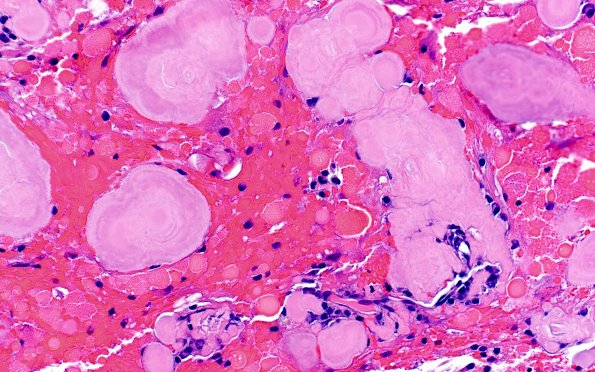

Washington University Experience | MISCELLANEOUS | Amyloidoma | 7B9 Amyloidoma (Case 7) H&E 40X 2

Additional examples of amyloid globules. (H&E) ---- Comment: Immunostains were performed by the outside institution and not sent for review. Per report, amorphous material is positive with Congo red. CD138 highlights plasma cells around amyloid and vessels. VS38c is positive in plasma cells. ISH lambda is positive and ISH kappa is negative, i.e. these are lambda-restricted plasma cells. CD20 is positive in patchy clusters of B cells. CD3 is positive in occasional perivascular and scattered small T cells. Synaptophysin is negative. GFAP highlights gliosis. CD163 shows a mild increase in macrophages/microglia. BRAF V600E is negative. IDH1(R132H) is negative. ATRX is retained. Immunostain for p53 highlights less than 5% of cells, consistent with a wildtype staining pattern. Ki-67 proliferation index highlights less than 1% of cells. Amyloid typing by mass spectrometry identified the amyloid as derived from lambda immunoglobulin light chains. Patients do not usually have any evidence of systemic amyloidosis and their brain lesions tend to grow slowly.